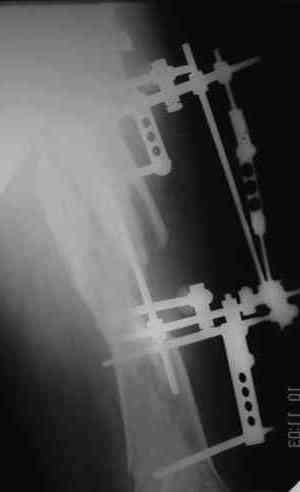

Уважаемые коллеги! Пришел на консультацию вот такой больной (первые 3-и рисунка). Травма автодорожная, апрель 2006г. Лечился консервативно, вытяжение и гипс. Через пять месяцев стал ходить. Укорочение бедра 6 см. 26 февраля 2007г. оступился, упал. Прооперирован в г.Баку - наложен стержневой аппарат. Ходит с костылями, наступая на левую ногу. Мы попросили что нибудь из ранних снимков. Принес рентгенограммы перелома (рис. 4,5). Посмотрели, наснимали сами (рис. 6-10). Похоже, что нет сращения нигде. Хотелось - бы обсудить следующие вопросы:1. дальнейшая тактика - реостеосинтез или подождать (ослабить аппарат, дать нагрузку и т.д.)?2. если реостеосинтез - то чем и как? Юрий Алексеевич Булахтин

Лучше бы закрытый интрамедуллярный, конечно.

Надо делать чрескожную подвертельную остеотомию, чтобы получился открытый клин. Проблемы будут и с формированием канала, надо развертки типа наших. Был как-то похожий случай, сделали одномоментно, сняли аппарат 5-месячый на столе, заштифтовали с подвертельной остеотомией (в приложении).

Можно все коррекции сделать и в аппарате, и потом заштифтовать, тогда останется только одна проблема формирования канала.